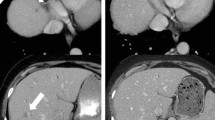

Subsequent publications confirmed, that resectability guidelines are not applicable on treated PDAC, since unchanged perivascular cuffs after neoadjuvant therapy are not correlated to resection margins [38] (Fig. 29.1).

Locally advanced PDAC under neo-adjuvant treatment. (a) Baseline image of a locally advanced PDAC in a 52-year-old female (arrowhead), with encasement of the superior mesenteric artery of >180° (arrow). (b) The same patient after neoadjuvant therapy with FOLFIRINOX. Considerable tumour shrinkage can be seen (arrowhead), however SMA encasement persists (arrow). The patient underwent total pancreatectomy with complete tumour dissection from the SMA and negative resection margins